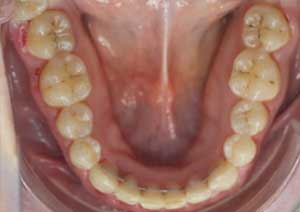

Le traitement de la supraclusion : Le traitement de la supraclusion repose avant tout sur un diagnostic précis, permettant de déterminer son origine dento-alvéolaire, squelettique ou mixte, ainsi que l’âge du patient.

Les objectifs principaux sont de réduire le recouvrement incisif, de rétablir une dimension verticale équilibrée et d’assurer une fonction occlusale stable.

Après